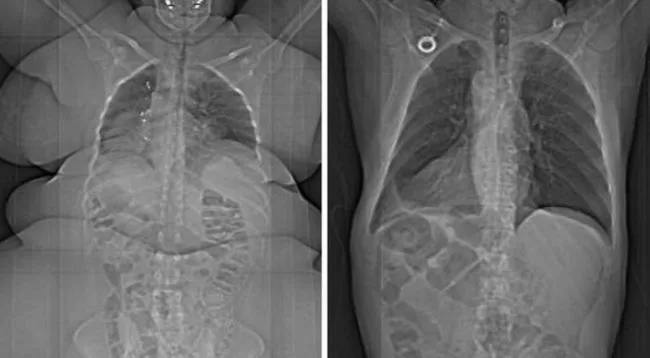

8 ภาพเอ็กซเรย์ระหว่างคนอ้วน กับคนที่ไม่มีภาวะอ้วน